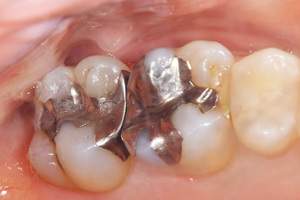

経年劣化していた銀歯

麻布十番歯科で銀歯の症例の口腔内写真

経年劣化していた銀歯の歯

麻布十番歯科で銀歯の中が虫歯になっている症例の口腔内写真